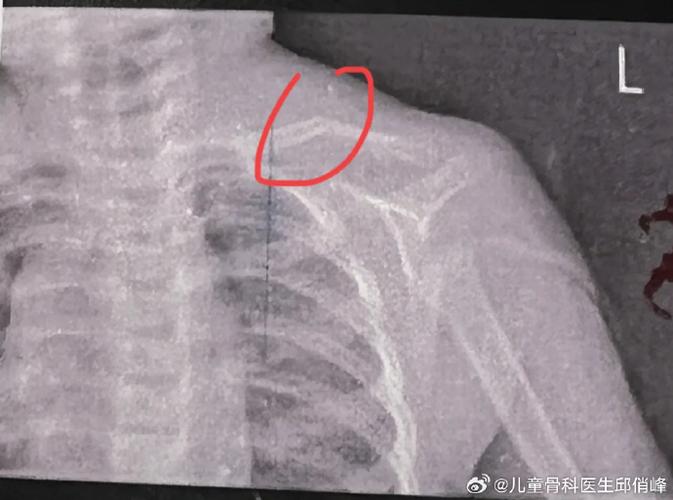

标签: 新生儿锁骨骨折护理注意事项 新生儿锁骨骨折正确睡姿方法